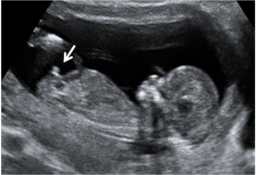

Ecografía de la semana 12

Los motivos por los que los ginecólogos recomiendan realizar una ecografía en la semana 12 de embarazo tienen que ver con el desarrollo anatómico y el tamaño del feto: ahora es lo bastante grande para comprobar si presenta anomalías. Además, ya se puede ver con claridad si hay uno o dos (o tres) bebés, calcular  la fecha probable de parto teniendo en cuenta la edad gestacional, y confirmar que esta coincide con el desarrollo del bebé. Se puede medir el llamado pliegue nucal (si sobrepasa unos parámetros a veces es indicio de problemas cromosómicos) y, si el bebé se deja, conocer su sexo.